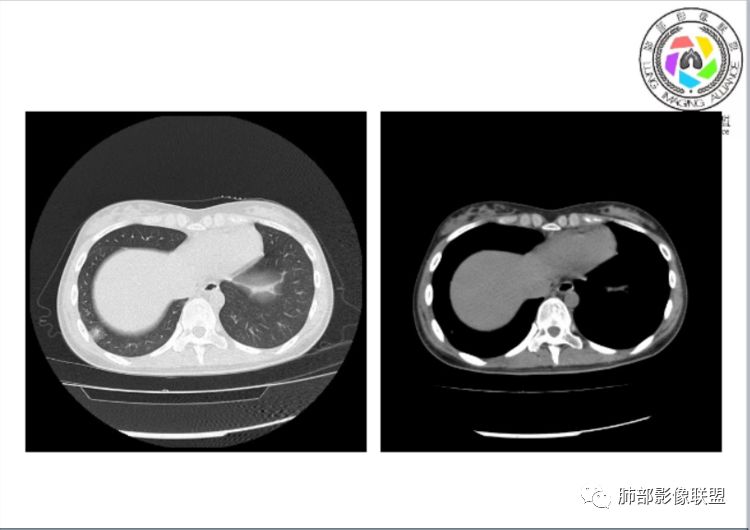

小微:右肺下叶斑片状密度增高影,抗炎治疗6天后复查,双肺下叶出现斑片状密度增高影,排除炎性病变,D2聚体特别高,考虑肺栓塞,肺梗死,建议增强扫描。王开金江津中心医院呼吸科:@岳微-辽宁PLA234医院放射科?支持,患者年轻女性,胸痛主诉,使用雌激素,高危人群,心率快,d二聚体升高,右下叶斑片加肺动脉明显增宽,抗感染无效,要考虑PTE,建议肺动脉ctpa。傅昌瑜:19岁,女性,右侧胸痛2天,发热以中度热为主,D—二聚体升高,肺动脉主干增宽,病灶位于胸膜下,抗感染后增多,近来有服用炔雌醇环丙孕酮片2周期史,诊断:肺栓塞,下一步完善肺CTPA检查。阿仙奴:青年女性,急性起病,胸痛入院,月经不调史,目前服用孕酮片。流感抗体阳性,d二聚体升高,无低氧血症。右肺下叶基底段胸膜下磨玻璃样改变,肺动脉增宽,治疗过程出现发热,复查左下叶胸膜下新发病灶。考虑:肺栓塞(服用孕酮相关)?奔跑的37°Doctor(陆喜红 ) :年轻女性,胸痛 急性病程,有服用雌激素避孕药史(是否有血液循环的改变,高凝状态),实验室D二聚体很高(也是提示血液高凝状态) ,第一次CT,右下肺胸膜下斑片状密度增高模糊影,肺动脉形态密度未见明显异常,抗炎后复查,肺动脉干及其分支,感觉增粗了一点,局部形态有点饱满,双下肺胸膜下片状影增多,锁定肺动脉栓塞应该不会错,建议CTA检查飞鹰行动:青年人,女性,右肺下叶斑片状密度增高影,抗炎治疗6天后复查无好转,,双肺下叶出现斑片磨玻璃影,主肺动脉增粗,结合患者服用的药物和D2聚体特别高,考虑肺栓塞,建议CTA。李:口服避孕药,有危险因素,肺动脉较主动脉增宽,D二聚体增高,胸膜下片状影,考虑肺栓塞;@晨义工张帅,医附属潞河医院呼吸?是否痰中带血很关键,不知有没有张帅:患者入院后第七天出现痰中带血风之子:病程中有发热,D—二聚体升高,肺动脉主干增宽,病灶分布于胸膜下,抗感染后增多,结合服药史诊断:肺栓塞,建议CTPA检查。不支持的地方是没有低氧血症,不明白为什么第二次复查ct双侧乳腺不对称,按理乳腺炎多见于哺乳期张帅:大家方向都在考虑肺栓塞:我提问两个问题:1 周围毛玻璃怎么回事?2左下肺小叶间隔增宽怎么回事?笨丫头:周围的磨玻璃应该考虑是肺梗死后出血渗出,同时合并机化性炎症小叶间隔增宽,我考虑应该是梗死后炎性渗出wonderful:我不支持肺栓塞 不能解释发热原因

水晶石头:患者青少年女性,右侧胸痛2天就诊。有咳嗽,无痰。初次胸部CT:右下肺片状模糊影。入院后经头孢美唑、莫西沙星抗感染治疗6天后复查胸部CT:右下肺病灶加重,且左下肺出现类似病灶。结合其气管镜气道无异常,病程中有发热,D—二聚体升高,近来因月经不调有服用炔雌醇环丙孕酮片史。诊断考虑良性非感染性。肺栓塞可能性大,鉴别血管炎及子宫内膜肺异位可能。流心明智:女性,19岁,右侧胸痛2天,中度热为主,D—二聚体升高,影像:肺动脉主干小于29mm,病灶位于右下肺胸膜下,斑片影,胸膜侧宽基底,抗感染后增多,左下肺亦出現类似病灶,似有反晕、融冰征。近来有服用炔雌醇环丙孕酮片2周病史,考虑诊断:肺栓塞。具体性质及发病机制有待进一步检查。尘缘:@吴永丽 灌云县医院 呼吸?应该是的,左下肺的磨玻璃影像后面也支持有出血改变所以可能就是一个子宫内膜异位出血合并感染

1、一个或多个胸膜下斑片高密度影(梗死、出血、肺不张、肺水肿、炎性渗出),典型为胸膜下楔形影 ,尖端指向肺门

2、肺动脉高压(中心肺动脉扩张),有时可见肺动脉区高密度影。

3.影像:病变胸膜下多发斑片影,提示与血管有关,早期病变为渗出,应该是早期的炎性渗出,病灶抗感染治疗后实变区增多、变大,临床症状又出现咯血,CT上应该合并了肺泡出血、梗死、肺不张及肺水肿;